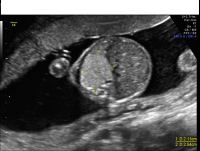

Bronchopulmonary sequestration axial